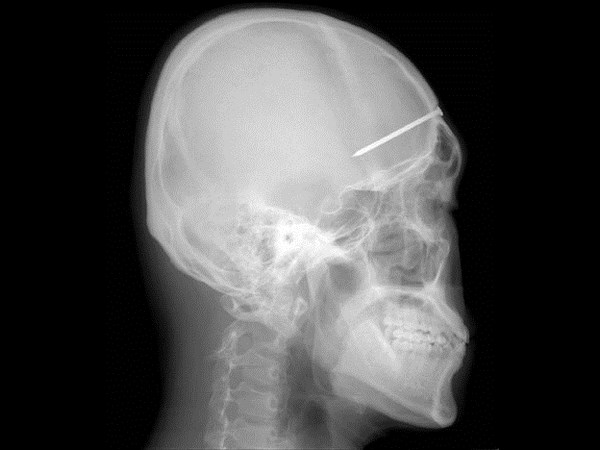

மருத்துவ உலகம் கண்டு வியந்த எக்ஸ் ரே படங்கள் இவைதான்

இதில் இவரது தலையில் ஊசி உள்ளது.